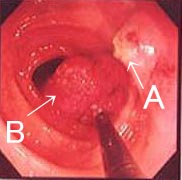

(4)切断したポリープを回収しています。黒い棒のように見えるのは『三脚』という細い器具で、切除したポリープ(B)をこれで保持しながら引抜きます。画面右上に断端(A)が見えます。 |